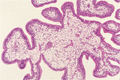

Macroscopic image:Many yellowish white polyps give the appearance of coral covering the mucosal surface.